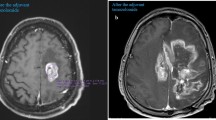

Previously, some reports mentioned that magnetic resonance imaging (MRI) can predict histopathological features in primary CNS lymphoma (PCNSL). The reported data analyzed diffusion-weighted imaging findings. The aim of this study was to investigate possible associations between histopathological findings, such as tumor cellularity, nucleic areas and proliferation index Ki-67, and signal intensity on T1-weighted and T2-weighted images in PCNSL.

For this study, 18 patients with PCNSL were retrospectively investigated by histogram analysis on precontrast and postcontrast T1-weighted and fluid-attenuated inversion recovery (FLAIR) images. For every patient, histopathology parameters, nucleic count, total nucleic area, and average nucleic area, as well as Ki-67 index, were estimated.

Correlation analysis identified several statistically significant associations. Skewness derived from precontrast T1-weighted images correlated with Ki-67 index (p = − 0.55, P = 0.028). Furthermore, entropy derived from precontrast T1-weighted images correlated with average nucleic area (p = 0.53, P = 0.04). Several parameters from postcontrast T1-weighted images correlated with nucleic count: maximum signal intensity (p = 0.59, P = 0.017), P75 (p = 0.56, P = 0.02), and P90 (p = 0.52, P = 0.04) as well as SD (p = 0.58, P = 0.02). Maximum signal intensity derived from FLAIR sequence correlated with nucleic count (p = 0.50, P = 0.03).

Histogram-derived parameters of conventional MRI sequences can reflect different histopathological features in PSNCL.